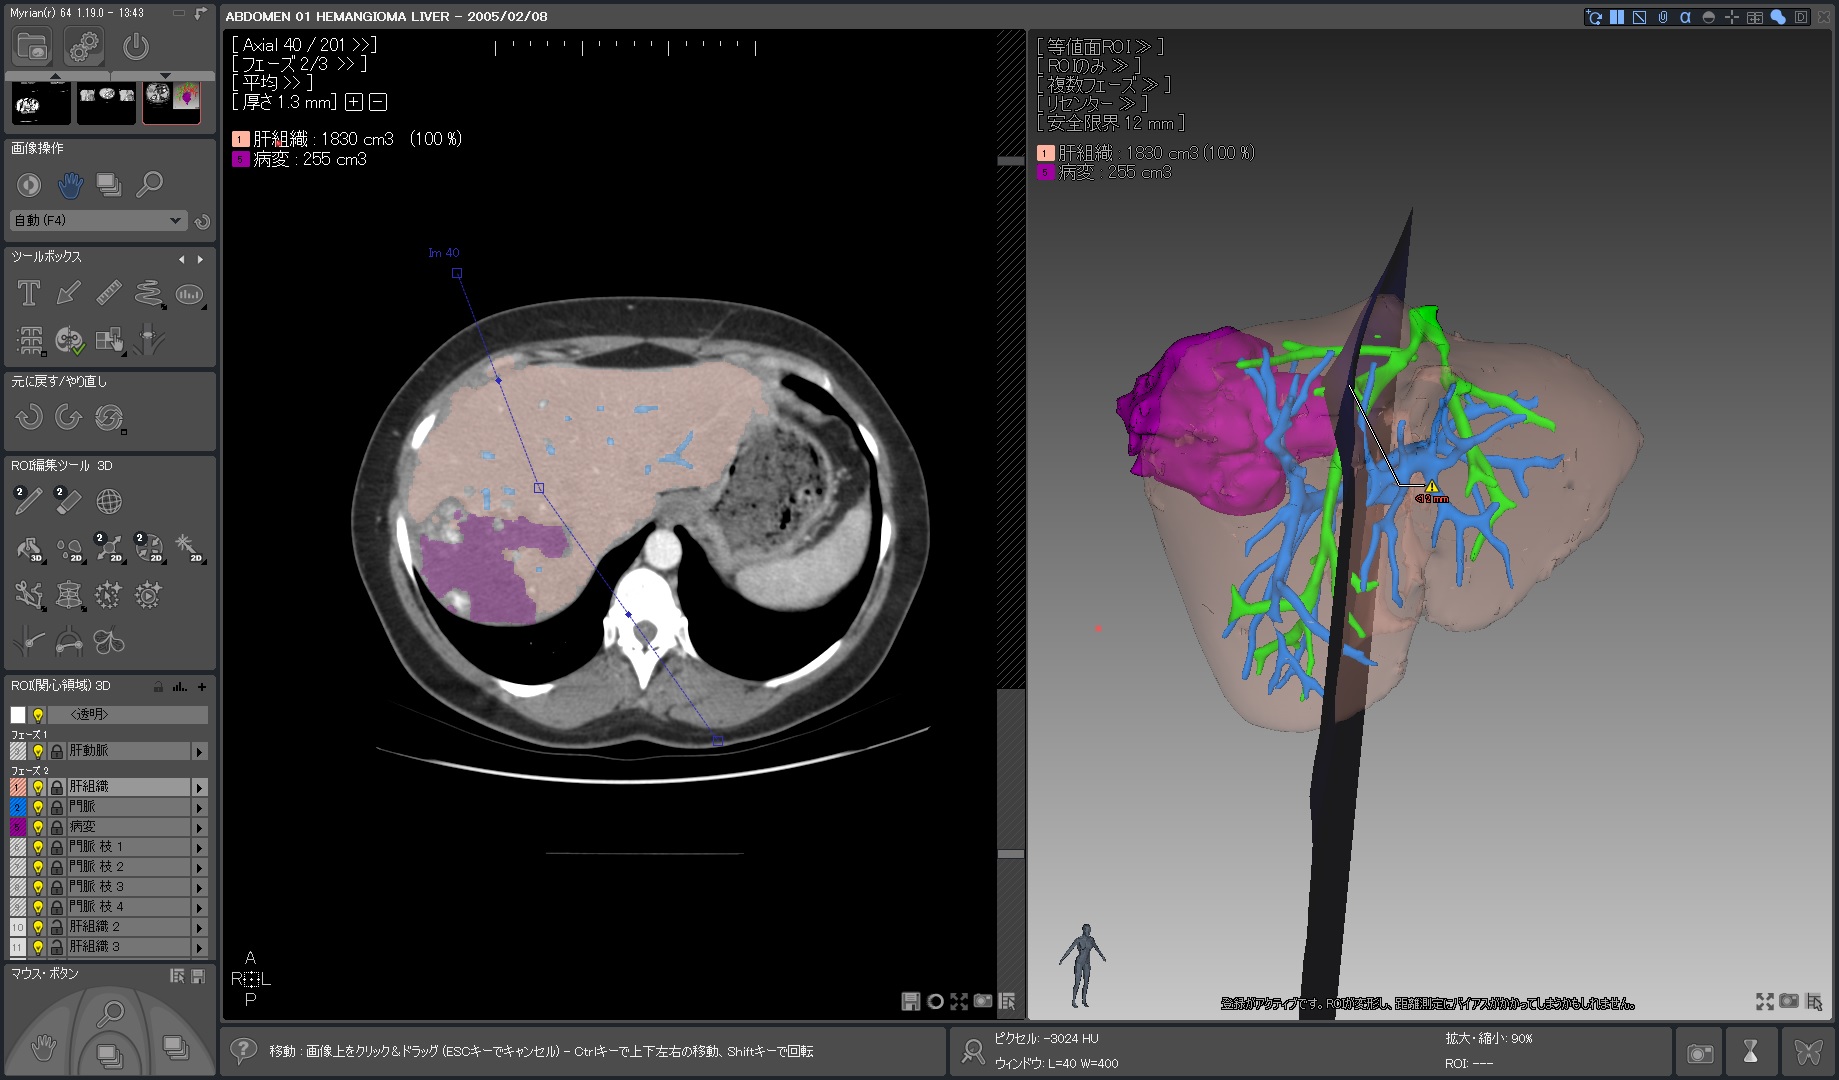

Myrian®XP-Liver 肝臓アプリケーション

世界的な実績と評価を得ている、肝臓解析と手術計画用ソフトウェア

独自に開発された、正確な非剛体レジストレーションと優れたセグメンテーション・アルゴリズムにより肝血管系、肝実質、腫瘍などを数秒で抽出します。

| 5.術前手術 シュミレーション |

|

|